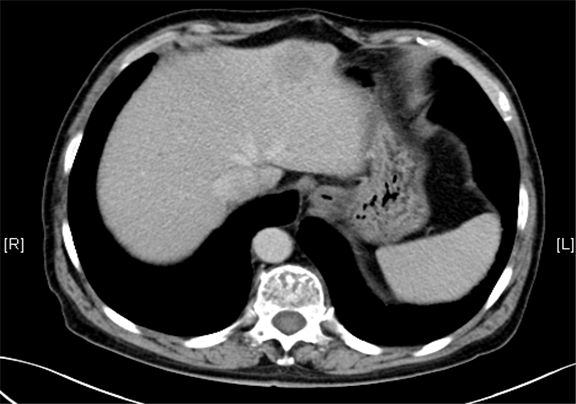

一般情况:CH-001-LT-000456, 63岁男性,身高170cm,体重77.00kg

主诉:查体发现肝占位性病变5月

现病史:患者5月前因“肝硬化”行上腹部CT发现肝占位性病变(未见报告),建议随访观察,患者无乏力、恶心、呕吐、腹胀、腹泻、血便、食欲减退,无寒战,无头痛头晕,无皮肤粘膜黄染,无尿频、尿急、尿痛、血尿。3天前再行上腹部增强CT检查示:肝左外叶占位,考虑恶性肿瘤伴门脉侵犯可能性大,建议MR平扫+强化符合肝硬化表现。双肾多发小囊肿可能性大

下腹部增强CT示:肝左外叶占位,考虑恶性肿瘤伴门脉侵犯可能性大,符合肝硬化表现。

术前CT检查:

静脉期